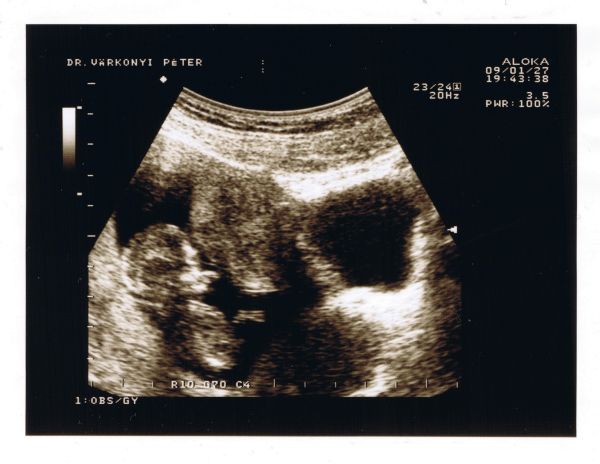

Most nézem!!!Nagyon jók a képek!!Hát igen!Egyértelműen fiúcska az a kis Pocaklakó!!!:)

Madaran:Örülök, hogy minden rendben volt a genetikai vizsgálaton!:)Akkor most már tuti a kisfiúcska?!?Nem sokára nálunk is kiderül, hogy fiúcskák vagy leányzók vagyunk!!!:)Már várom a jövő hetet!!:)